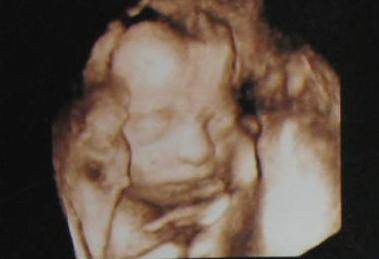

其实以上的两种方法都是猜测的一种,可能几率比其它的大。主要判断男友还是B超,大部分孕妈四个月的时候,孩子的生殖器官就形成了,这个时候如果用三维B超查看性别,那真的很准。为什么不说普通B超呢?因为有时候还在在肚子乱动可能手啊什么的会挡住生殖器,所以用三维就最好的。